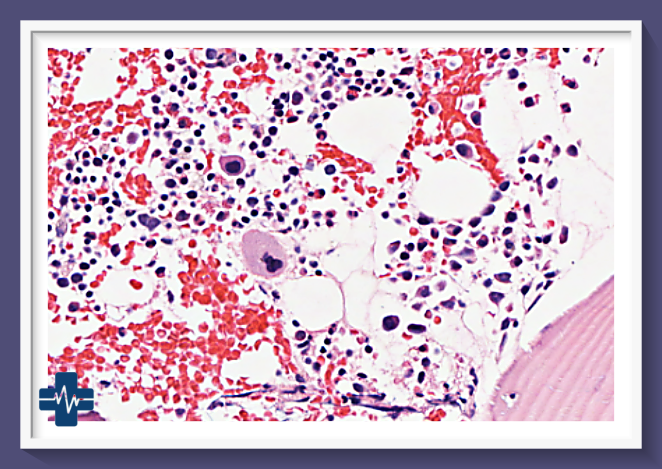

골수암, 특히 급성 및 만성 골수성 백혈병은 혈액암의 한 유형으로, 골수에서 비정상적인 백혈구가 과도하게 생산되는 질환입니다. 이 질환은 골수의 정상적인 기능을 방해하여 다양한 신체적 증상을 유발하며, 진단과 치료가 시급한 중대한 건강 문제입니다.

골수암, 특히 다발성 골수종과 급성 골수성 백혈병은 혈액암의 주요 유형으로, 골수에서 비정상적인 혈액 세포의 과도한 증식을 특징으로 합니다. 이러한 암의 생존율은 다양한 요인에 의해 영향을 받으며, 최근 몇 년간 치료법의 발전으로 인해 개선되고 있는 추세입니다.

다발성 골수종은 혈액암 중 하나로, 골수에서 형질세포가 악성화하여 과증식하는 질환입니다. 최근 통계에 따르면, 다발성 골수종의 5년 생존율은 약 50.7%로 보고되었으며, 이는 1993~1995년의 23.7%에 비해 두 배 이상 향상된 수치입니다. 이러한 개선은 신약 개발과 치료법의 진보에 기인합니다. 특히, 재발 환자의 경우 적절한 치료 조합이 중요하며, 첫 번째 재발 시의 치료 효과가 환자의 예후를 좌우하는 것으로 알려져 있습니다.